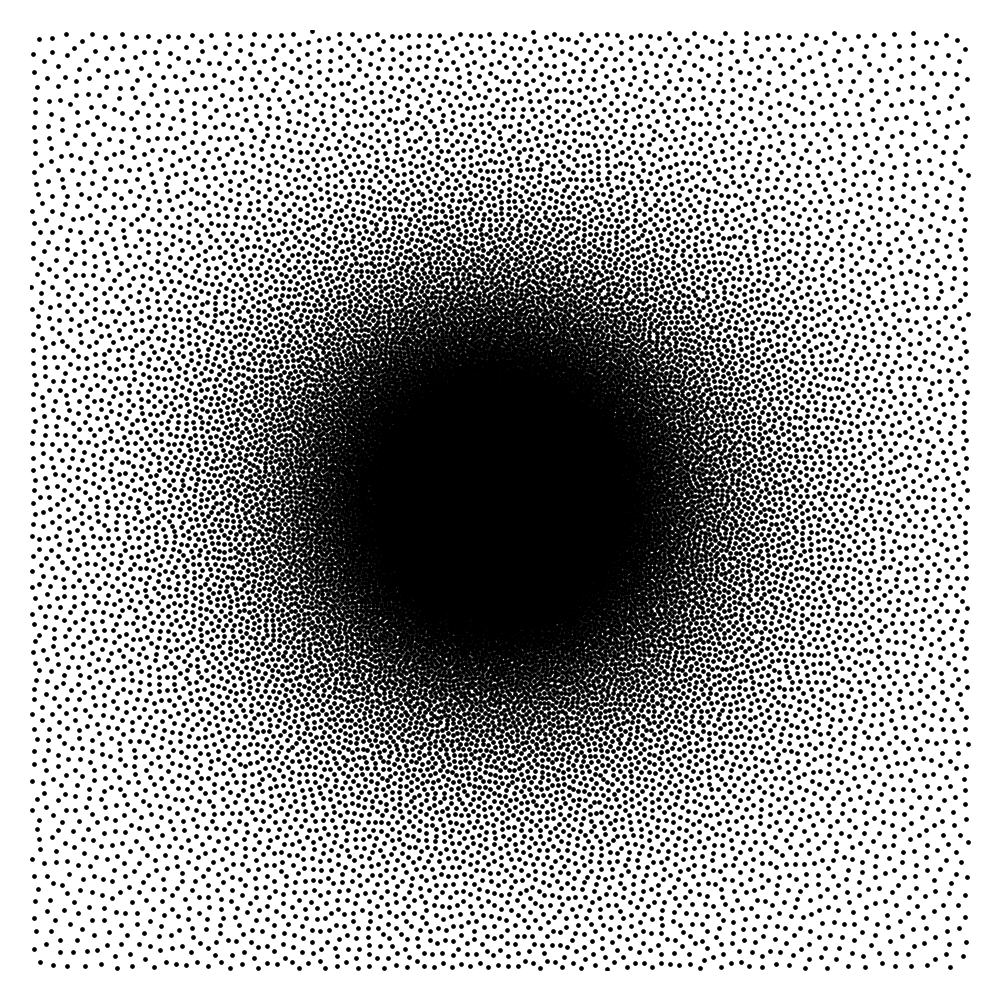

where the expectation is taken with respect to the noise term . A schematic illustration of this approach is proposed in Fig. 2.

The elements in this family are good candidates for sampling densities: i) they are nearly constant and approximately equal to at the center of the k-space, ii) they can be anisotropic to accommodate for specific image orientations and iii) they have various decay rates, allowing sampling the high frequencies more or less densely. Some examples of such densities are displayed in Fig. 3(a). However, the family of densities generated by this procedure is quite poor. For instance, it is impossible to sample densely both the and axes simultaneously. In order to enrich it, we propose to consider the set of convex combinations of these elementary densities. This allows us to construct more general multi-modal densities, see Fig. 3(b) for examples of such convex combinations.

In order to construct the family , we first draw a large family of densities . They are generated at random by uniform draws of the parameters inside a box. We then perform a principal component analysis (PCA) on this family to generate some eigen-elements . We set . Since probability densities must sum to , we orthogonalize the family with respect to the vector . Thereby, we obtain a second family that satisfies and for all . This procedure discards one dimension. The resulting PCA basis is illustrated in Fig. 3(c).